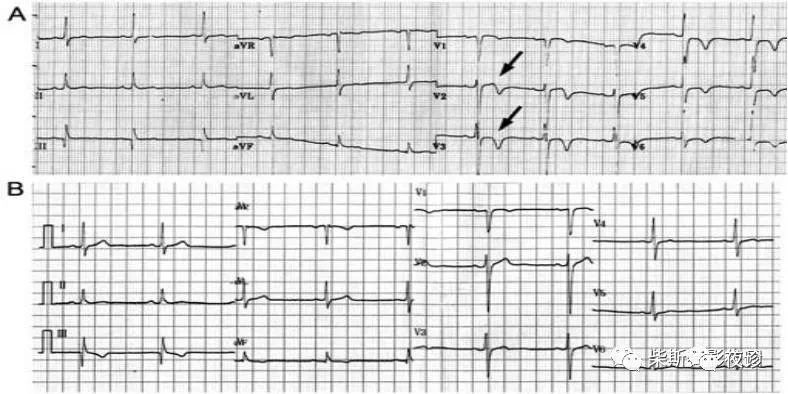

演变过程中会出现的巨大倒置T波,其可持续数日或更长时间后变浅或转为低平、直立。

巨大倒置T波幅度增大,倒置T波形态窄,顶部尖锐,内角变小且;

T波双支常呈对称性倒置成“冠状T”

④ 心绞痛缓解后出现T波对称性深倒置或正负双向,以后逐渐转为直立的动态演变过程,持续时间数小时至数周不等。

特指脑血管意外患者出现的一种特殊形态的巨大倒置T波,此T波还可见于交感神经过度兴奋的其他疾病,如各种急腹症、神经外科手术后、心动过速后、肺动脉栓塞、二尖瓣脱垂等。该波由交感神经过度兴奋引起,常见于中胸及左胸导联,即V3~V6导联,亦见于肢体导联,巨大倒置T波宽深倒置、不对称,常有切迹,而且与其他巨大倒置的T波不同,尼加拉瀑布样T波的演变迅速,可持续数日自行消退。

患者胸前导联T波倒置的发生率为40%,特别是大面积肺栓塞时,胸前导联T波倒置最出现频率高,T波倒置最常出现在V1~V3导联,可延伸至V1~V6、V3R、V4R导联。T波多对称性倒置,似“冠状T波”,深度一般自右向左逐渐变浅,且呈动态演变。